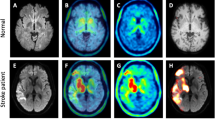

Cerebral MRI

At one- and seven- years follow-up, MRI scans were acquired on a Philips Intera system 1.5 T (Philips Medical Systems, Best, The Netherlands). The MRI study protocol consisted of 3D-T1, axial T2, 3D-FLAIR, DWI and SWI sequences.

MRI investigations were evaluated for focal vascular lesions, medial temporal lobe atrophy (MTLA), white matter lesions (WML), and global cortical atrophy (GCA), by two radiologists, blinded to the clinical information. Any discrepancies were resolved by consensus. MTLA was graded from 0 to 4; with MTLA grade 0 = no atrophy, MTLA 4 = highest degree of atrophy. MTLA 0–1 is considered normal [55]. WML was rated using the visual rating scale proposed by Fazekas, scores ranging from 0 to 3 [56]. GCA was rated using the visual rating scale known as Pasquier scale, ranging from 0 to 3 [57].

18F-Flutemetamol PET CT acquisition

Qualitative classification of 18F-Flutemetamol PET

Quantitative classification of 18F-Flutemetamol PET

Motion correction of the 18F-Flut PET was performed using frame-by-frame rigid registration, then the frames were summed to a single time-frame image and rigidly registered to the anatomical MRI volume using a 6-parameter rigid registration as implemented in the Statistical Parametrical Mapping (SPM 12, Wellcome Trust Centre for Neuroimaging, UCL, UK) toolbox. 18F-Flut-PET standardized uptake value ratios (SUVr) were obtained by normalization to the brainstem. Both the cerebellar cortex, pons and brainstem are widely used Flutemetamol reference regions, acquiring amyloid build plaques not until the fifth and final phase of amyloid deposition [61]. Our choice of reference region was influenced by local tradition, a feeling that the structural masks of the cerebellar cortex were less accurate, and a long series of publications utilizing the brainstem or pons as reference region. Prior to normalization, the brainstem mask was eroded by 1 mm to avoid partial volume effects, inaccurate segmentation or co-registration. 18F-Flut-PET uptake was analyzed in five pre-selected cortical regions of interest (ROIs), as defined by Desikan et al. [62] and implemented in FreeSurfer as described above, known to hold substantial amyloid plaques in AD: the precuneus and posterior cingulate combined, anterior cingulate, prefrontal, inferior parietal, and lateral temporal cortex [63]. The 18F-Flut-PET uptake for each region was averaged across the hemispheres. We further calculated a composite SUVr by averaging the uptake in the above-mentioned regions. SUVr were not calculated to categorize scans as positive or negative but used as continuous variables in correlation analyses.